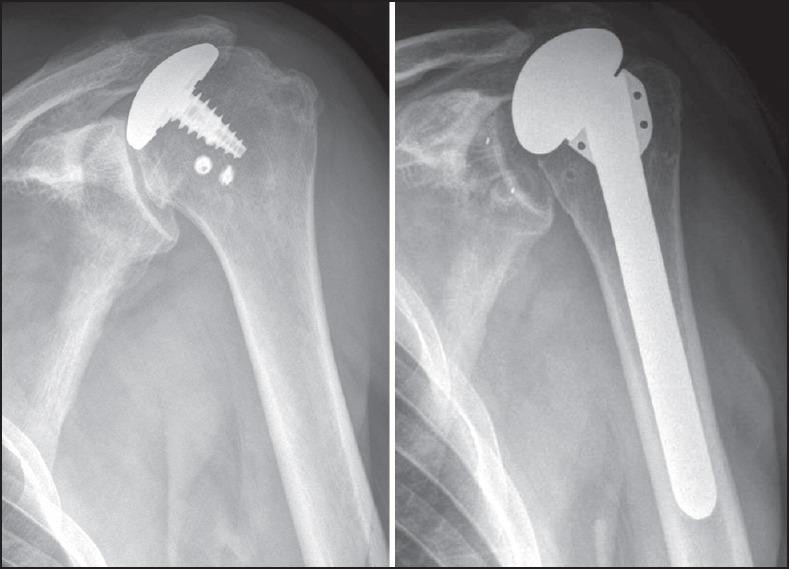

MATERIALS AND METHODS

All patients were revised to stemmed arthroplasties, including one hemiarthroplasty, two reverse, and eight anatomic total shoulder arthroplasties at a mean 33 months after primary resurfacing (range 10-131 months). A deltopectoral approach was used in seven patients; four patients required an anteromedial approach due to severe scarring. Subscapularis attenuation was found in four cases, two of which required reverse total shoulder arthroplasty. Bone grafting was required in one glenoid and three humeri.

材料与方法

所有患者均翻修为带柄关节成形术,包括1例半关节成形术、2例反向和8例解剖型全肩关节成形术,初次表面置换后平均33个月(范围10 - 131个月)。7例患者采用三角肌胸大肌入路;4例患者因严重瘢痕需要采用前内侧入路。4例发现肩胛下肌减弱,其中2例需要行反向全肩关节成形术。1例关节盂和3例肱骨需要植骨。